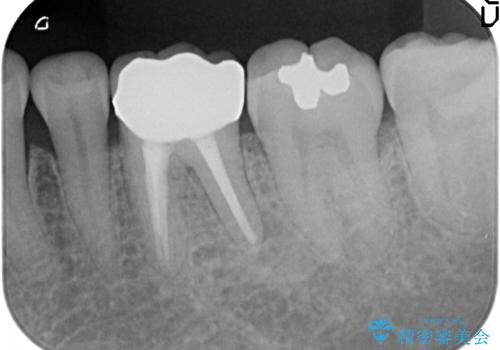

- 他院にて左下6の再根管治療を勧められ当院にいらっしゃった方の症例です。

再根管治療終了後、オールセラミッククラウンにて補綴を行いました。

今回用いたオールセラミッククラウンはジルコニアフレームという白い素材の上にセラミックを盛っているため、審美性が非常に高いのが特徴です。

また、ジルコニアは人工ダイヤモンドの材料にも使われているほど高い強度を持っており、そのためオールセラミッククラウンは審美性だけでなく、奥歯やブリッジの補綴も可能とするクラウンです。